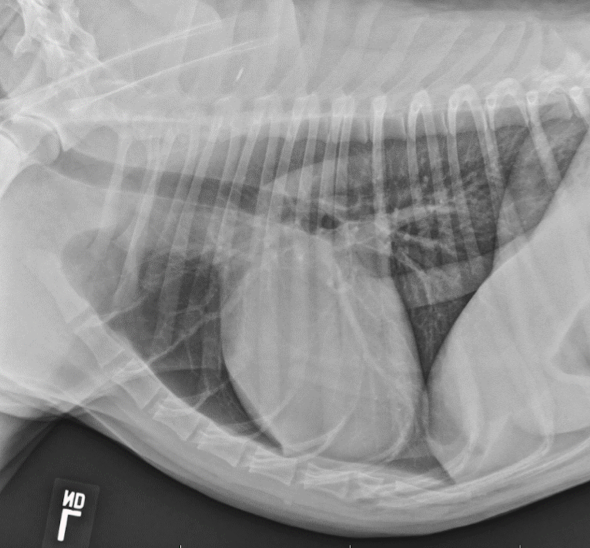

13

Juvenile idiopathic megaesophagus

14